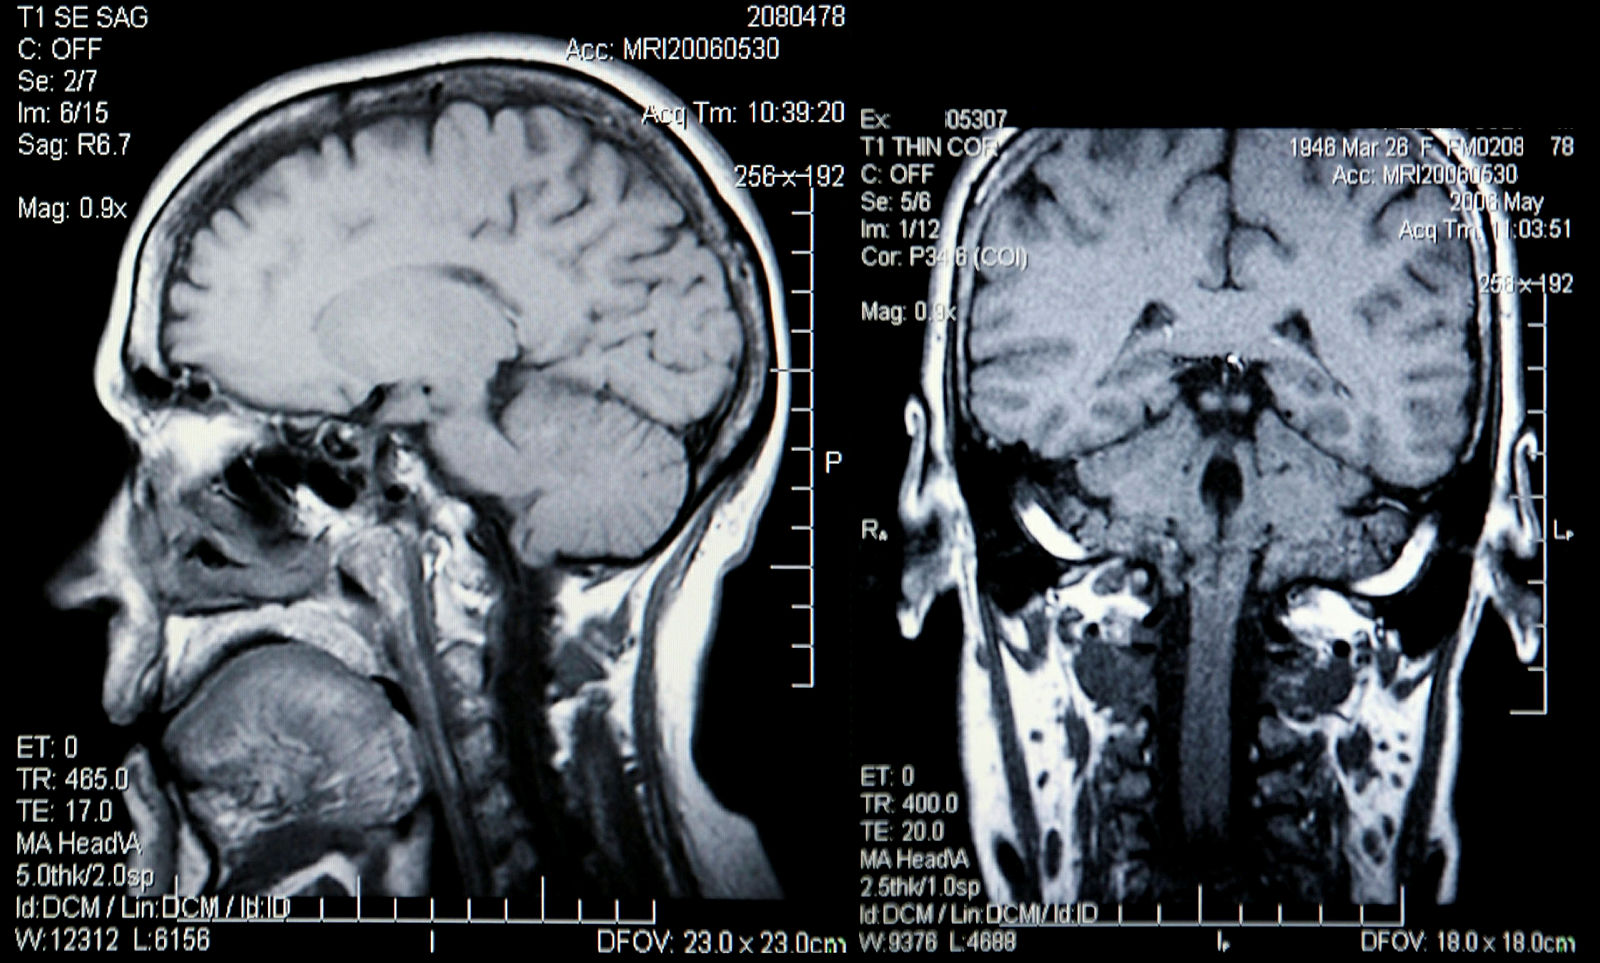

Røntgenbilde av hodeskalle

Mangel på godkjenning, utstyr gått ut på dato og røntgenapparat i loftsstuen var noe av det Helsetilsynet avdekket.